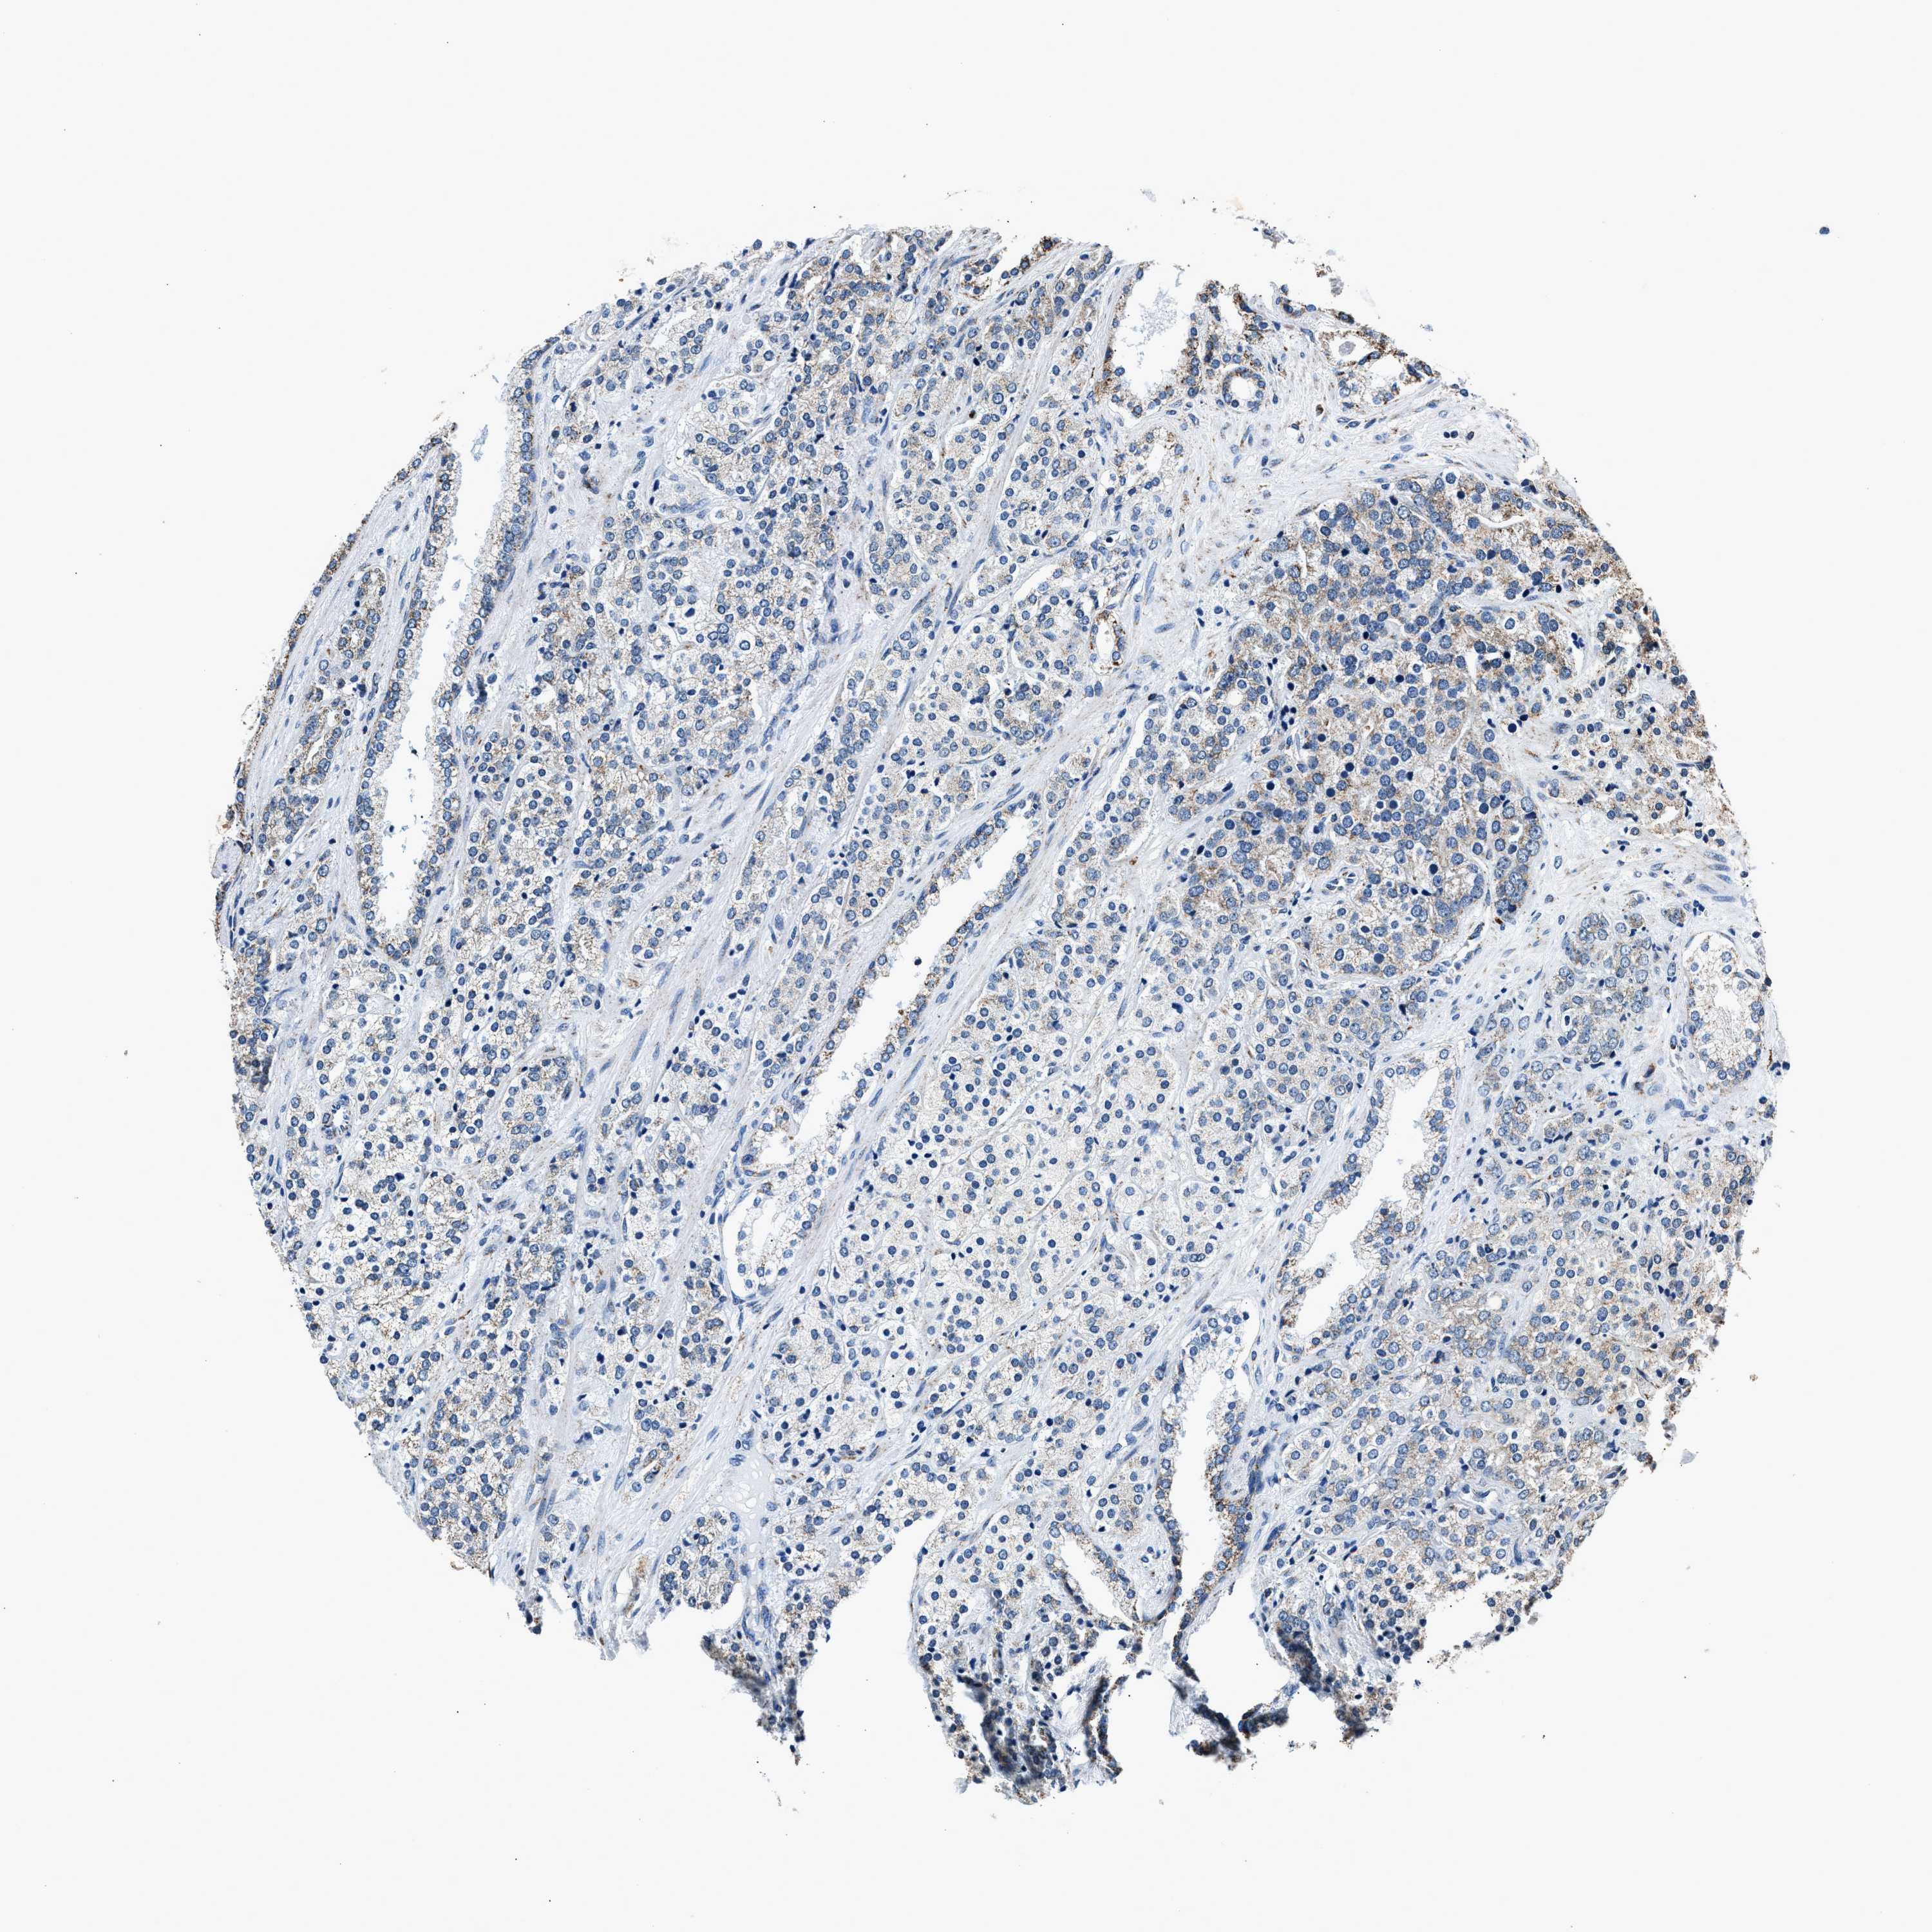

PROSTATE CANCER - Protein expressioni

A mouse-over function shows sample information and annotation data. Click on an image to view it in a full screen mode. Samples can be filtered based on level of antibody staining by selecting one or several of the following categories: high, medium, low and not detected. The assay and annotation is described here.

Antibody stainingi

Antibody staining in the annotated cell types in the current human tissue is reported as not detected, low, medium, or high, based on conventional immunohistochemistry profiling in selected tissues. This score is based on the combination of the staining intensity and fraction of stained cells.

Each image is clickable and will lead to virtual microscopy that enables deeper exploration of all samples and also displays staining intensity scores, fraction scores and subcellular localization as well as patient and tissue information for each sample.

Antibody HPA019522

Antibody HPA021002

Staining

High

Medium

Low

Not detected

Intensity

Strong

Moderate

Weak

Negative

Quantity

>75%

75%-25%

<25%

None

Location

Nuclear

Cytoplasmic/membranous

Cytoplasmic/membranous,nuclear

Adenocarcinoma, High grade

Adenocarcinoma, Low grade